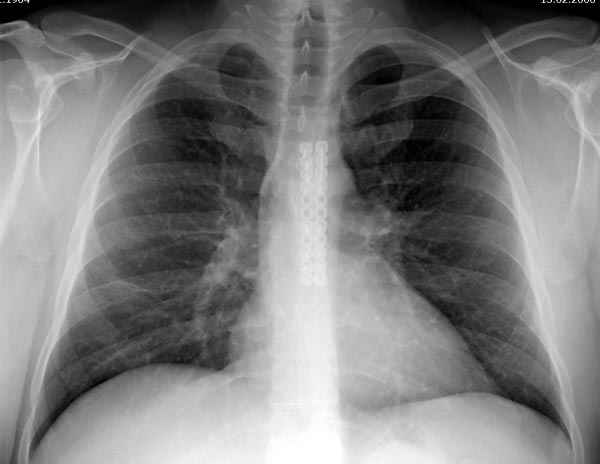

Оперировали вместе с грудным хирургом и в нашем случае главной причиной была болезненность. Во время операции приняли все меры предосторожности недопущения прокола средостения (см. на 4 снимке близкий контур сердца!!)

Ложный сустав зафиксирован двумя пластинами 2.4 мм (locking plate) позаимствованными из челюстно-лицевой хирургии, с костной пластикой, все остальные пластины мне показались слишком толстыми, грубые для грудины или отсутсвовали возможности создания угловой стабильности.

Рентген снимки во время операции и последние сделаны на днях.